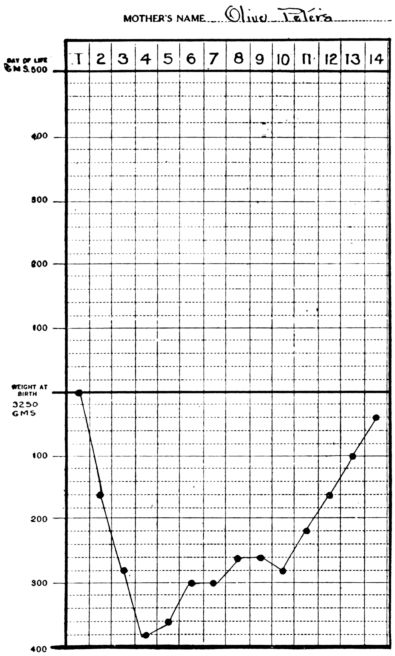

| 6. | Showing normal daily gain in weight during first two weeks | 520 |

| 7. | Showing loss of weight in inanition fever contrasted with No. 6 | 520 |